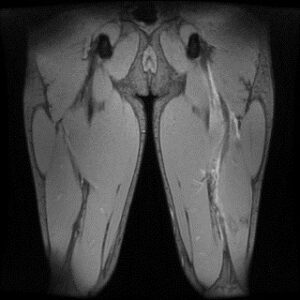

• MRI検査:より深部の損傷や、完全断裂の疑いがある場合の詳細な評価、重症度評価を行います。

*右:筋膜(黒)の連続性がない     左:ハムストリング筋内に沿って広範に損傷、出血している